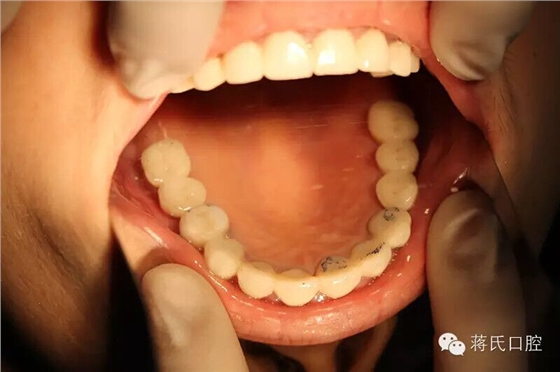

17.修復(fù)完成的冠

18.修復(fù)完成后口內(nèi)